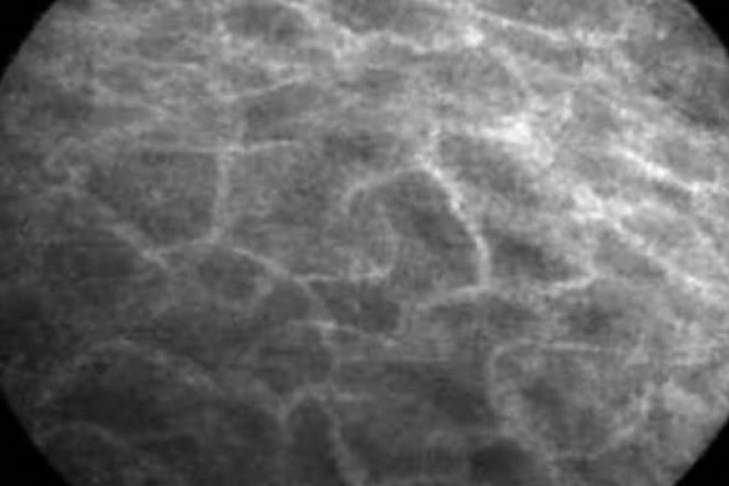

Сеть каналов была обнаружена случайно во время эндоскопии, когда врачи осматривали изнутри желудочно-кишечный тракт пациента. Разглядывая желчный проток, они обнаружили, что окружающие его ткани не плотные и однородные, как считалось ранее, а пронизаны сетью неизвестных каналов. Сначала исследователи решили, что перед ними просто капилляры, но в таком случае сами капилляры, заполненные жидкостью, при микроскопическом исследовании должны быть затемнены, а ткань между ними быть более светлой. Однако перед учеными была совершенно противоположная картина.

Изучив ткани других органов, в том числе носа, исследователи выяснили, что каналы проходят и через них. Ученые предполагают, что эти каналы, по которым циркулирует жидкость, могут затрагивать все ткани в организме и являться новым органом, в котором содержится до 1/5 всей жидкости организма.